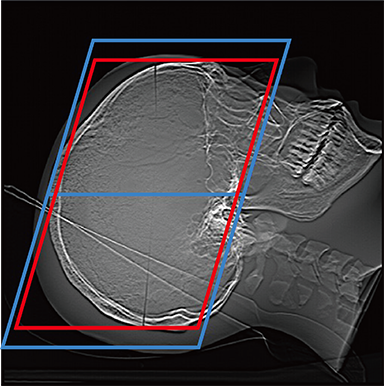

FCT iStream automatically*2 sets the scanning range using the scanogram image by AutoPose function. Since the margins can be set in advance, the range can be customized according to the preference of the facility. iTilt automatically creates and enables observation of tilted images during scanning.

When set to OM Line

When set to SM Line

When set to RB Line

Red: automatically set position, Blue: automatically set position + margin setting position